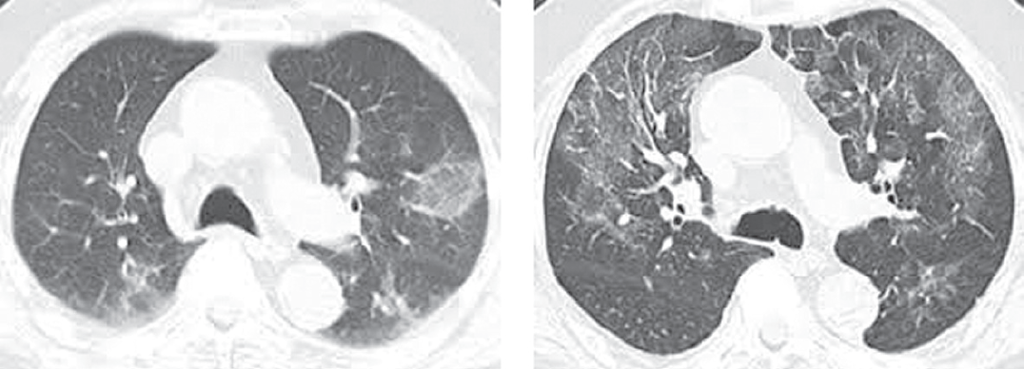

Рентгенографическая (томографическая) картина легких может оставаться нормальной в течение всей болезни. У части пациентов в фазе респираторных расстройств выявляются очаговые инфильтраты в легочной ткани с тенденцией к увеличению размеров и слиянию, вовлечением в патологический процесс интерстициальной ткани (по типу «матового стекла») (рис. 4). Локализуются инфильтраты преимущественно в нижних и средних зонах легких. Также может присутствовать небольшой плевральный выпот.

Рис. 4. Компьютерная томограмма органов грудной клетки — двусторонние инфильтраты в легочной ткани по типу «матового стекла» [5]

Fig. 4. CT of the chest organs – bilateral infiltrates in the lung tissue according to the type of «frosted glass» [5]